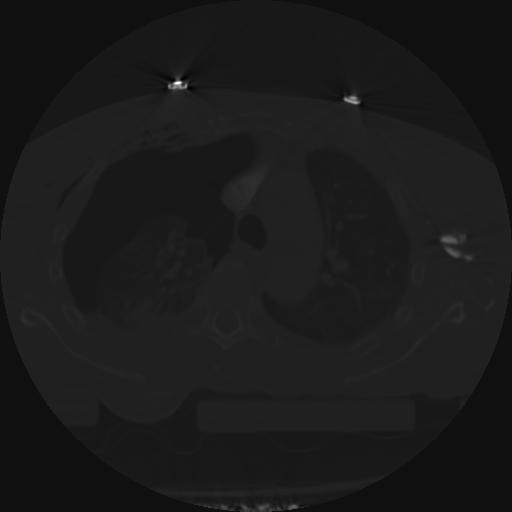

21 ANGIO,CE,Axial,3.0,ANGIO,,